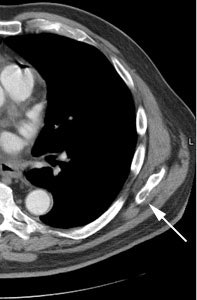

Unsuspected bone metastases: The patient shown below had a cavitary left lung non-small cell lung cancer. There was no uptake of tracer within the aortopulmonary window lymph nodes detected on CT to suggest metastases, however, unsuspected bone metastases were found in the left anterior 4th rib (black arrow) and lumbar spine (red arrows- not included in staging lung CT scan). The presence of bone metastases significantly alters patient prognosis and management. PET imaging provides a rapid whole body survey for the detection of unsuspected metastatic disease. |

|